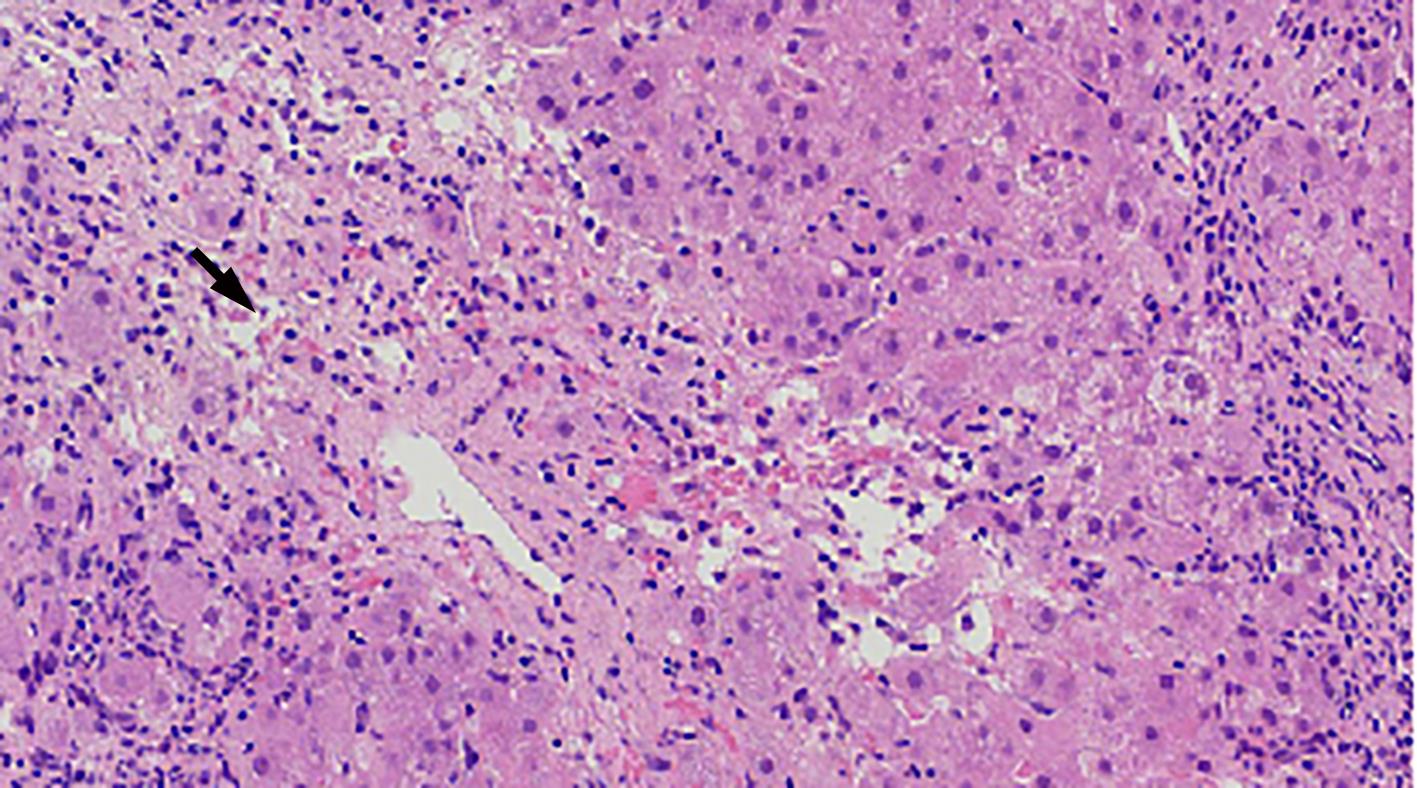

Alcoholic liver disease (ALD) is a liver disease caused by long-term heavy drinking. With the improvement in the living standard of Chinese people, the incidence rate of ALD tends to increase significantly. The typical pathological patterns of ALD include alcoholic steatosis, alcoholic steatohepatitis, liver fibrosis, and alcoholic cirrhosis. The diverse and complex pathological morphology of ALD and its similarities with other liver diseases pose a great challenge to pathologists. This article reviews the histopathological morphology, grading and staging systems, and differential diagnosis of ALD.